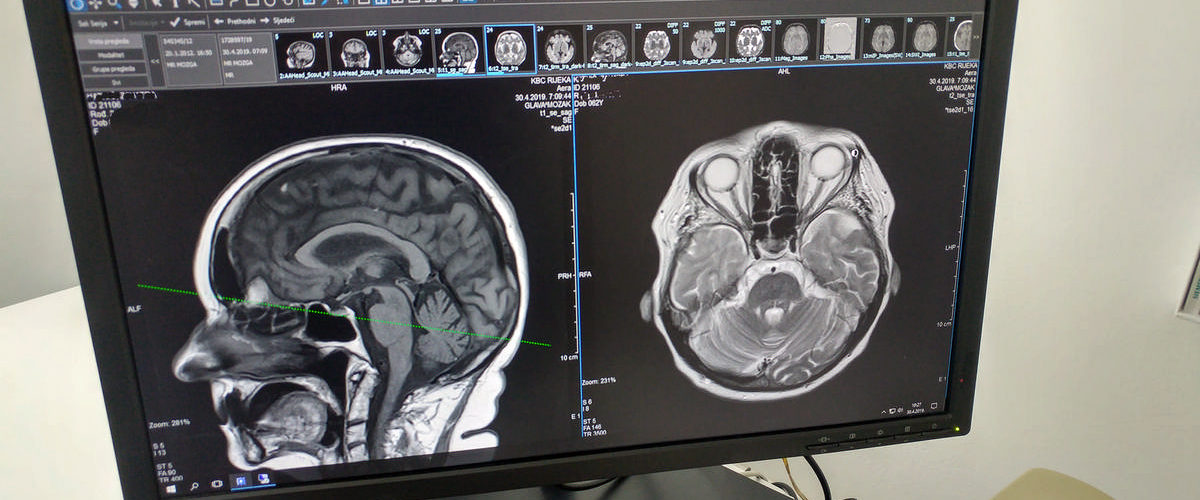

Kratkotrajni i dugoročni neurološki učinci COVID-19 još uvijek se prate s obzirom na veliki broj neuroloških manifestacija ne samo u akutnoj fazi nego i dugo nakon preboljele infekcije. Post COVID 19 neurološki sindrom je postvirusni sindrom uzrokovan odgovorom mozga i tijela na infekciju virusa, SARS-CoV-2.

Karakteriziraju ga produljena pojava depresije, razne neuromuskularne bolesti poput slabosti mišića i miopatija, tjeskobe, umor, poremećaji spavanja, različiti kognitivni problemi, problemi s koncentracijom, pažnjom, pamćenjem, kao i vrtoglavica, glavobolja, gubitak mirisa, bolesti pokreta, epilepsije, cerebrovaskularne bolesti i drugo.